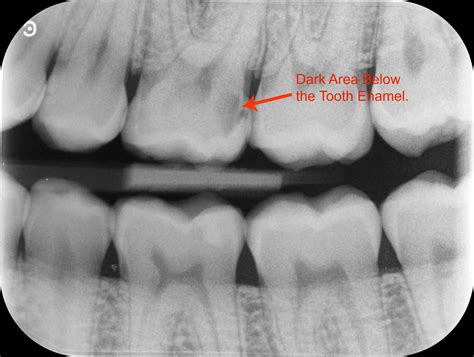

• Cavities and tooth decay

• Enhanced Diagnostic Accuracy: The detailed images provided by Crown X Ray Dental technology allow dentists to make more accurate diagnoses, leading to better treatment plans.